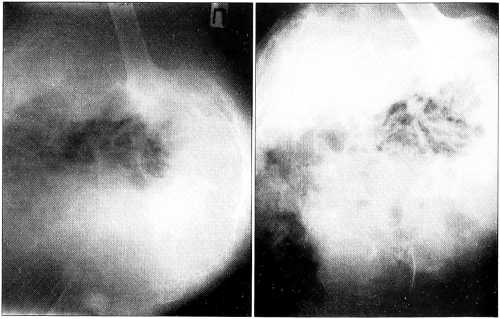

Больной С., 59 лет. За 4 года до поступления в больницу № 62 оперирован в одном из ортопедических учреждений Харькова по поводу ошибочно диагностированного остеохондроза, грыжи Шморля поясничного отдела позвоночника. Был выполнен спондилодез металлическими пластинами. Боли сохранялись, и через несколько лет была выявлена хондросаркома с поражением костей левой половины таза. Опухоль распространялась от крыла подвздошной кости до уровня пупка, а кверху — до половины расстояния от подвздошной кости до реберной дуги (рис. 1, а). Отмечались нарушение (затруднение) мочеиспускания и задержка стула. Больной консультирован повторно в различных учреждениях Харькова, Киева и Москвы, где признан неоперабельным по распространенности процесса: считалось, что опухоль прорастает мочевой пузырь и прямую кишку. При этом не учитывались особенности течения хондросарком, которые обычно не склонны к инфильтрации окружающих тканей и органов. В процессе роста эти опухоли, как правило, отодвигают прилежащие органы и ткани, не прорастая их. Общеизвестно также, что хондросаркомы нечувствительны к лучевому воздействию и химиотерапии и для больных этой категории единственным адекватным лечением является радикальное хирургическое вмешательство.

С учетом этих обстоятельств больному 22.07.70 была произведена операция — межподвздошнобрюшная ампутация (рис. 1. б). Мочевой пузырь и прямая кишка сдавливались опухолью, которая заполняла полость малого таза, но не прорастала их. Морфологическое заключение: хондросаркома средней степени зрелости. В послеоперационном периоде у больного развился мочевой свищ в связи с тем, что по ходу операции была перевязана пузырная артерия и на небольшом участке произошел некроз стенки мочевого пузыря. В последующем свищ был ликвидирован хирургическим путем, функция мочевого пузыря и прямой кишки восстановилась. В течение 19 лет пациент находился под наблюдением, отмечал хорошее самочувствие и полную адаптацию к жизни.

Рис. 1. Рентгенограммы больного С. Хондросаркома тела подвздошной кости. а — до операции; б — после операции.